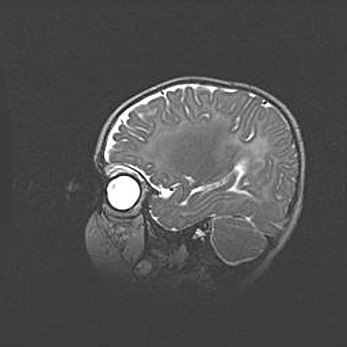

Подострая гематома правой гемисферы мозжечка.

Наружная гидроцефалия.

Возраст: 15 дней

Вес: 3100 г

Пол: женский

Окружность головы: 37 см

Срок гестации: 35-36 недель

При открытой наружной форме гидроцефалии у новорожденных расширяются и переполняются субарахноидные пространства.

Кровоизлияния в мозжечок имеют две клинико-анатомические формы: полушарные гематомы и кровоизлияния в червь.

К появлению этой патологии может привести: повреждения головного мозга, возникающие в результате асфиксии и гипоксии плода при беременности, или травмы во время родов. Редко гематома мозжечка может быть результатом первичной коагулопатии и сосудистой мальформации, диссеминированном внутрисосудистом свертывании, изоиммунной тромбоцитопении.